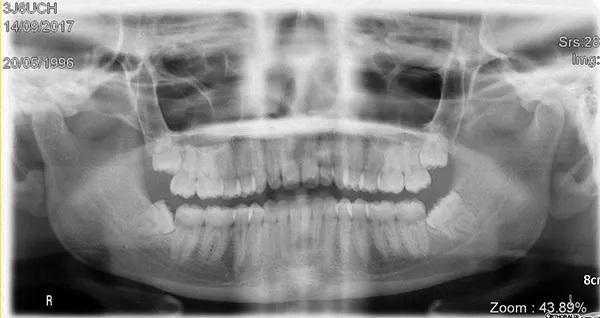

На панорамной рентгенограмме был обнаружен пораженный левый третий моляр нижней челюсти с тремя корнями и аномально большой коронкой (Фото 1). Необычная морфология зуба позволяла предположить, что это был случай сращения третьего моляра со сверхкомплектным зубом (то есть четвертым моляром).

Фото 1: Панорамная рентгенограмма, на которой виден “двойной зуб” в положении левого нижнего импактного третьего моляра.